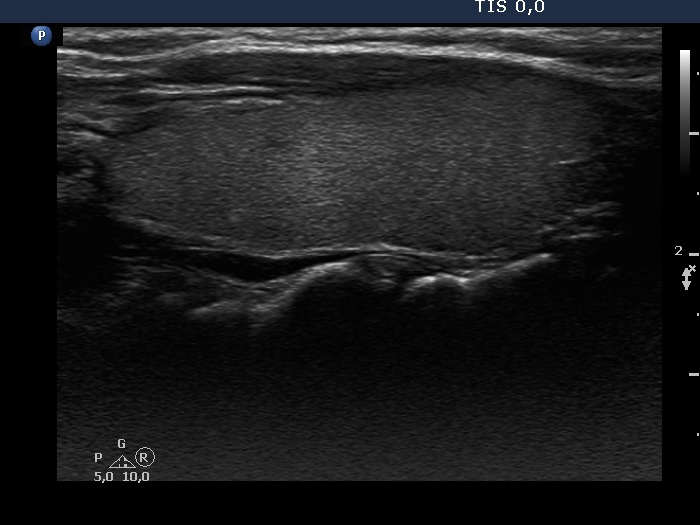

Consecutive patients with the final diagnosis of Hashimoto's thyroiditis - case 26 (805) (ultrasonographic picture 2)

Right lobe, longitudinal scan.